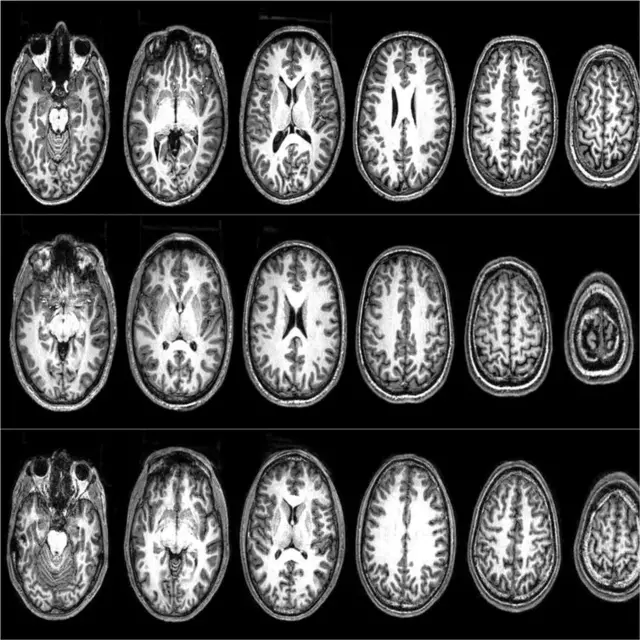

Para los escáneres cerebrales utilizamos una técnica llamada imagen por resonancia magnética funcional (IRMf), que registra e identifica las áreas del cerebro que están activas durante tareas específicas.

Nuestro primer estudio de IRMf analizó qué hace que los valores no sagrados se transformen en sagrados.

Desde un punto de vista neurológico, los valores sagrados activaron el giro frontal inferior izquierdo, una zona asociada con el procesamiento de normas, y ya relacionada anteriormente con los valores sagrados en estudiantes universitarios estadounidenses.

Sin embargo, en el caso de los que habían resultado excluidos aumentó la disposición a luchar y morir por valores no sagrados, y el giro frontal inferior izquierdo se activó incluso durante el procesamiento de los valores no sagrados.

Fuente de la imagen, Frontiersin

En otras palabras, la exclusión social hizo que los valores no sagrados resultaran más similares a los valores sagrados.

Este es un cambio alarmante, ya que sugiere que la exclusión social contribuye a que las actitudes sean menos transigentes y aumente la tendencia a la violencia.

Estos participantes mostraron un patrón diferente de actividad neuronal con respecto a los marroquíes del primer estudio, que tenían los mismos patrones que los estudiantes universitarios de Estados Unidos.

A medida que los hombres pakistaníes altamente radicalizados iban evaluando sus valores sagrados, se produjo una desactivación en una red que incluye la corteza dorsolateral prefrontal (DL-PFC), una zona del cerebro que se asocia con el razonamiento deliberativo y la integración de cálculos de coste-beneficio.

Cuando calificaron como alta la disposición para luchar y morir por sus valores, descubrimos un aumento de la activación en la corteza prefrontal ventromedial (VM-PFC), una zona del cerebro que se asocia con la valoración subjetiva (¿cuánto valor tiene esto para mí?).

En el día a día, estas dos zonas del cerebro trabajan de forma conjunta en la toma de decisiones.

En un análisis de seguimiento se descubrió que esas dos regiones del cerebro estaban muy conectadas cuando los participantes calificaban como baja su disposición para luchar y morir; es decir, el valor subjetivo estaba limitado por los mecanismos de control de costes y beneficios.

Pero cuando calificaban como alta la disposición para luchar y morir, descubrimos que esas dos regiones estaban más desconectadas.

Esto sugiere que, cuando alguien está listo para matar o morir en defensa de una idea, ya no utiliza los mecanismos de control que suelen participar en el razonamiento deliberativo.

Básicamente, desconectan esta parte del cerebro. Sin embargo, su disposición para luchar y morir disminuye a medida que las regiones de valoración deliberativa y subjetiva se vuelven a conectar. Entonces, ¿qué mecanismos llevan a las personas a reducir su disposición para luchar y morir por una causa?